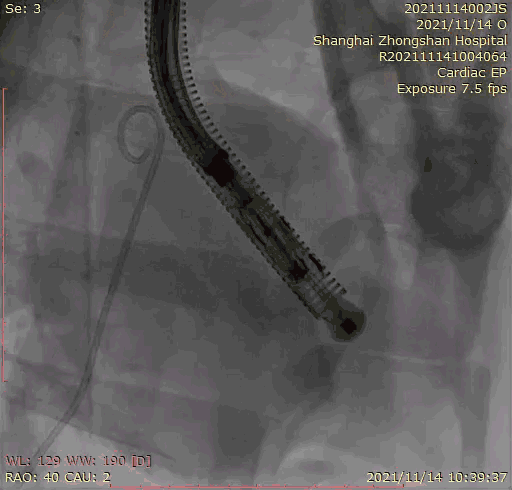

上海中山醫院葛均波院士、錢菊英院長、周達新教授、潘文志教授、潘翠珍教授、李偉教授共同完成此次臨床前研究。術后葛均波院士對Lux-Valve Plus的器械操作性能給予了高度評價,DSA和超聲影像也顯示出在本次研究中Lux-Valve Plus的安全性和有效性俱佳。

本次臨床前研究經右側頸靜脈置入LuX-Valve Plus輸送系統可調彎鞘管,在DSA及超聲引導下將人工三尖瓣瓣膜植入到原有三尖瓣位置,利用獨特的錨定技術將人工瓣膜支架可靠固定在預定的位置。